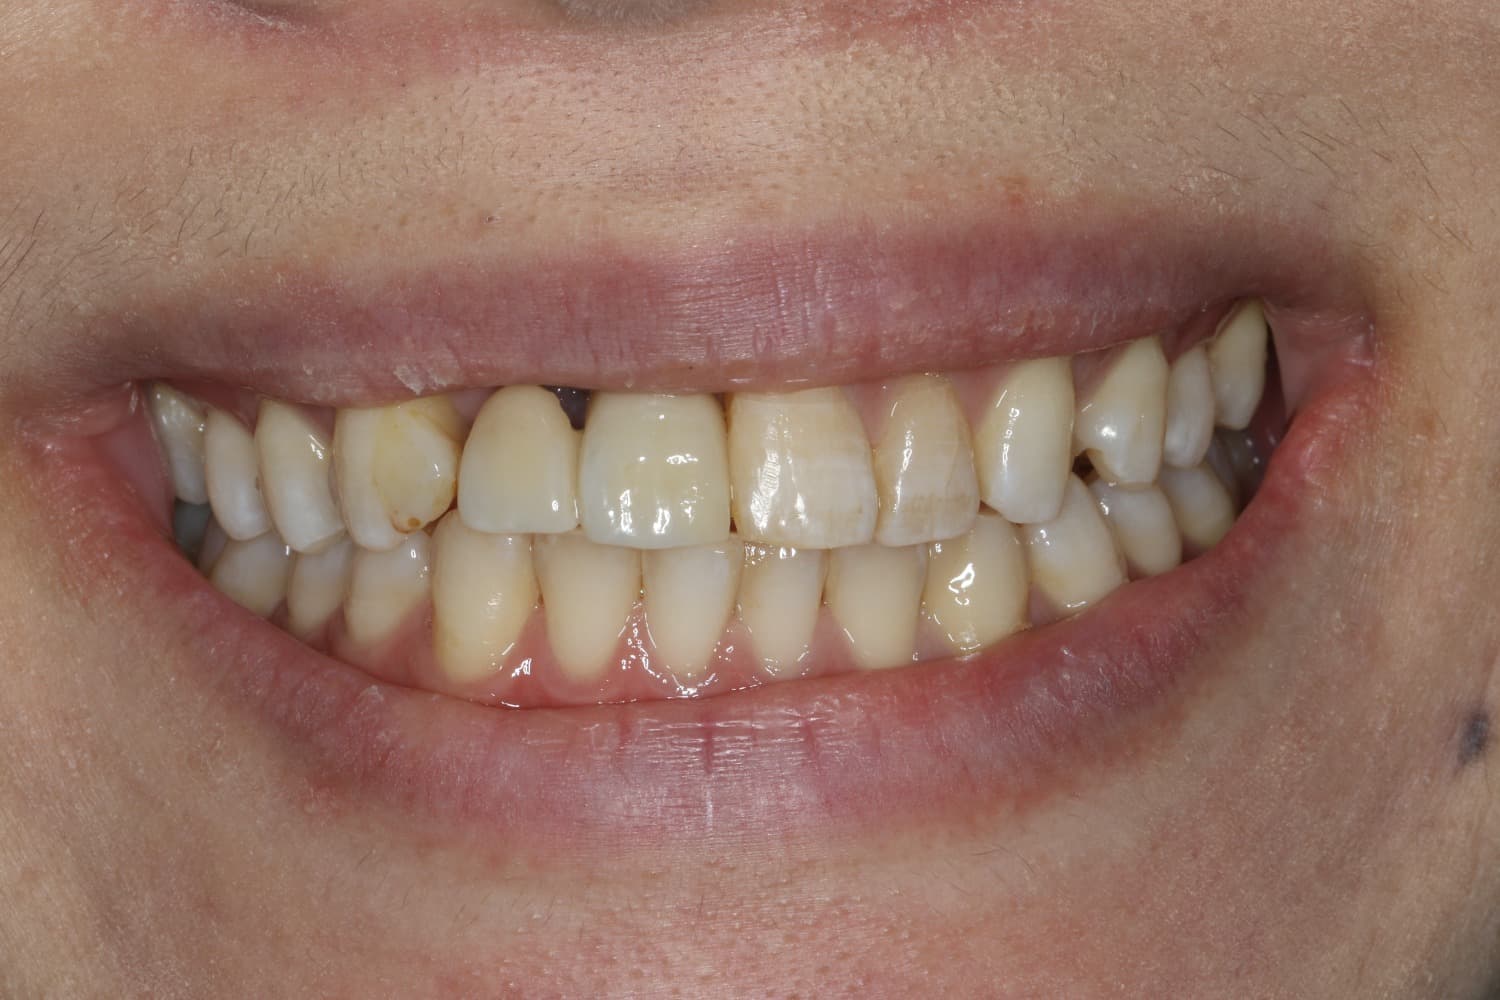

Before

After

喪失した連続欠損に対してインプラントGBRCTGを行い、審美的・機能的に回復を行なった

年齢

30代

性別

男性

主訴

前歯の入れ歯を避けたいのでインプラントをしてほしい

治療期間

2年

治療回数

20回

費用

200万円

副作用・リスク

腫脹、疼痛